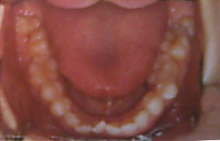

以前他の歯医者さんでとってもらった写真があるのですが、この歯並びでもインビザラインで治せますか?

問題なくインビザラインで治せる症例です。

歯並びはインビザラインで綺麗になりますよ!いつでもご相談ください。

問題なくインビザラインで治せる症例です。

歯並びはインビザラインで綺麗になりますよ!いつでもご相談ください。